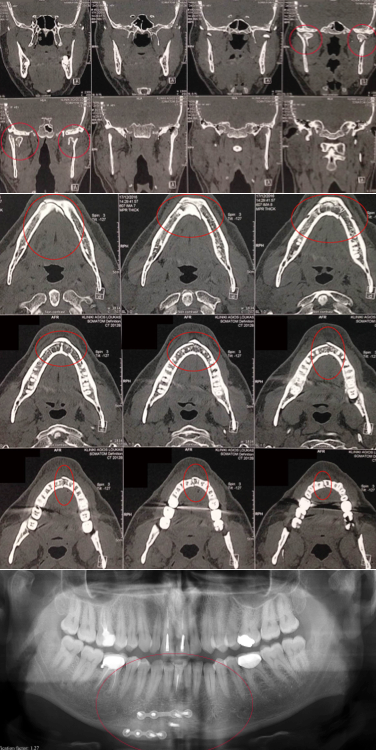

Η ιδιαιτερότητα των οστών του κρανίου και κυρίως του σπλαχνικού ως υμενογενή, προσδίδουν την ανάγκη για άμεση και γρήγορη όσο το δυνατόν αντιμετώπιση, λόγω της συντομότερης πόρωσής τους από τα άλλα οστά του ανθρώπινου σκελετού. Η καθυστέρηση χρονικά στην αντιμετώπιση των καταγμάτων του σπλαχνικού κρανίου, θα οδηγήσει πιθανόν σε φλεγμονές με αποστήματα, κακή πόρωση, ψευδάρθρωση, αδυναμία μάσησης και οδοντικής σύγκλισης, ασυμμετρία και παραμόρφωση του προσώπου, υπαισθησίες ή παραισθησίες νεύρων του προσώπου, κακή ανάταξη των καταγμάτων με πιθανή υποτροπή τους.

Επίσης Τα τελευταία χρόνια, αυξημένος παρουσιάζεται ο αριθμός των αυτόματων καταγμάτων σε ασθενείς που λαμβάνουν φάρμακα (διφοσφωνικά) για την οστεοπόρωση ή την οστεοπενία, αλλά και σε ασθενείς που λαμβάνουν θεραπείες για νεοπλάσματα (πχ χημειοθεραπείες). Γίνεται λοιπόν κατανοητό, πόσο σημαντική είναι η όσο το δυνατόν γρηγορότερη χρονικά παρέμβαση με ανάταξη των οστών του σπλαχνικού κρανίου σε περίπτωση καταγμάτων του.

Οι τεχνικές οστεοσύνθεσης με μικρού μεγέθους πλάκες είναι σήμερα οι πλέον συνήθης. Μεταλικές ή και απορροφήσιμες πλάκες τοποθετούνται ανάλογα με την περίπτωση του κατάγματος. Πολλές φορές χρειάζεται και δεύτερη παρέμβαση, λόγω καθυστερημένης χρονικά ανάταξης του κατάγματος, για τη διόρθωση της όχι καλής πόρωσης ή σύγκλισης του τραύματος, με χρήση διαφόρων ιστών όπως οστικό μόσχευμα από το κρανίο ή το ανώνυμο οστό. Με το πλεονέκτημα της καλής γνώσης των οστών του κρανίου το αποτέλεσμα είναι στην πλειονότητα το ευνοϊκότερο.